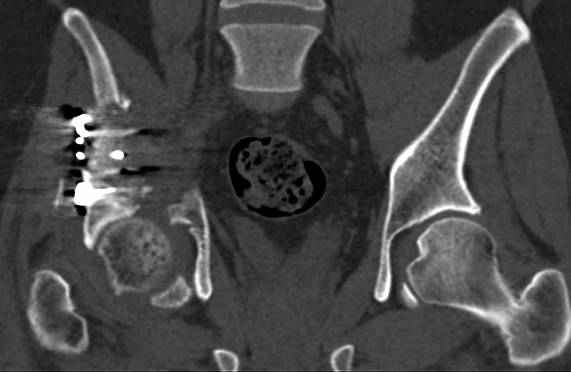

высылаю дополнительно сканы.

Судя по представленным реконструкциям (не очень хорошего качества - много наводок)

По отдельным срезам и тем более по реконструкции трудно судить о сращении крыла и задней колонны с осевым скелетом.

В большинстве случаев при двухколонных переломах

в итоге получается прочный бублик с дыркой. При эндопротезировании в дырку помещается головка, а чашка должна неплохо заклиниться в бублике.

Главное, чтобы бублик не был разорван, что не очень понятно на представленных снимках.

Хорошо бы на рентгенограммы взглянуть и побольше срезов по своду. С каким отломком головка контактирует и как ее состояние.

Из того минимума, что представлено, мне кажется, мы имеем дело с двухколонным переломом вертлужной впадины. Обычно медиальный (центральный) "вывих" головки встречаются в сложных двухколонных переломах со смещением.